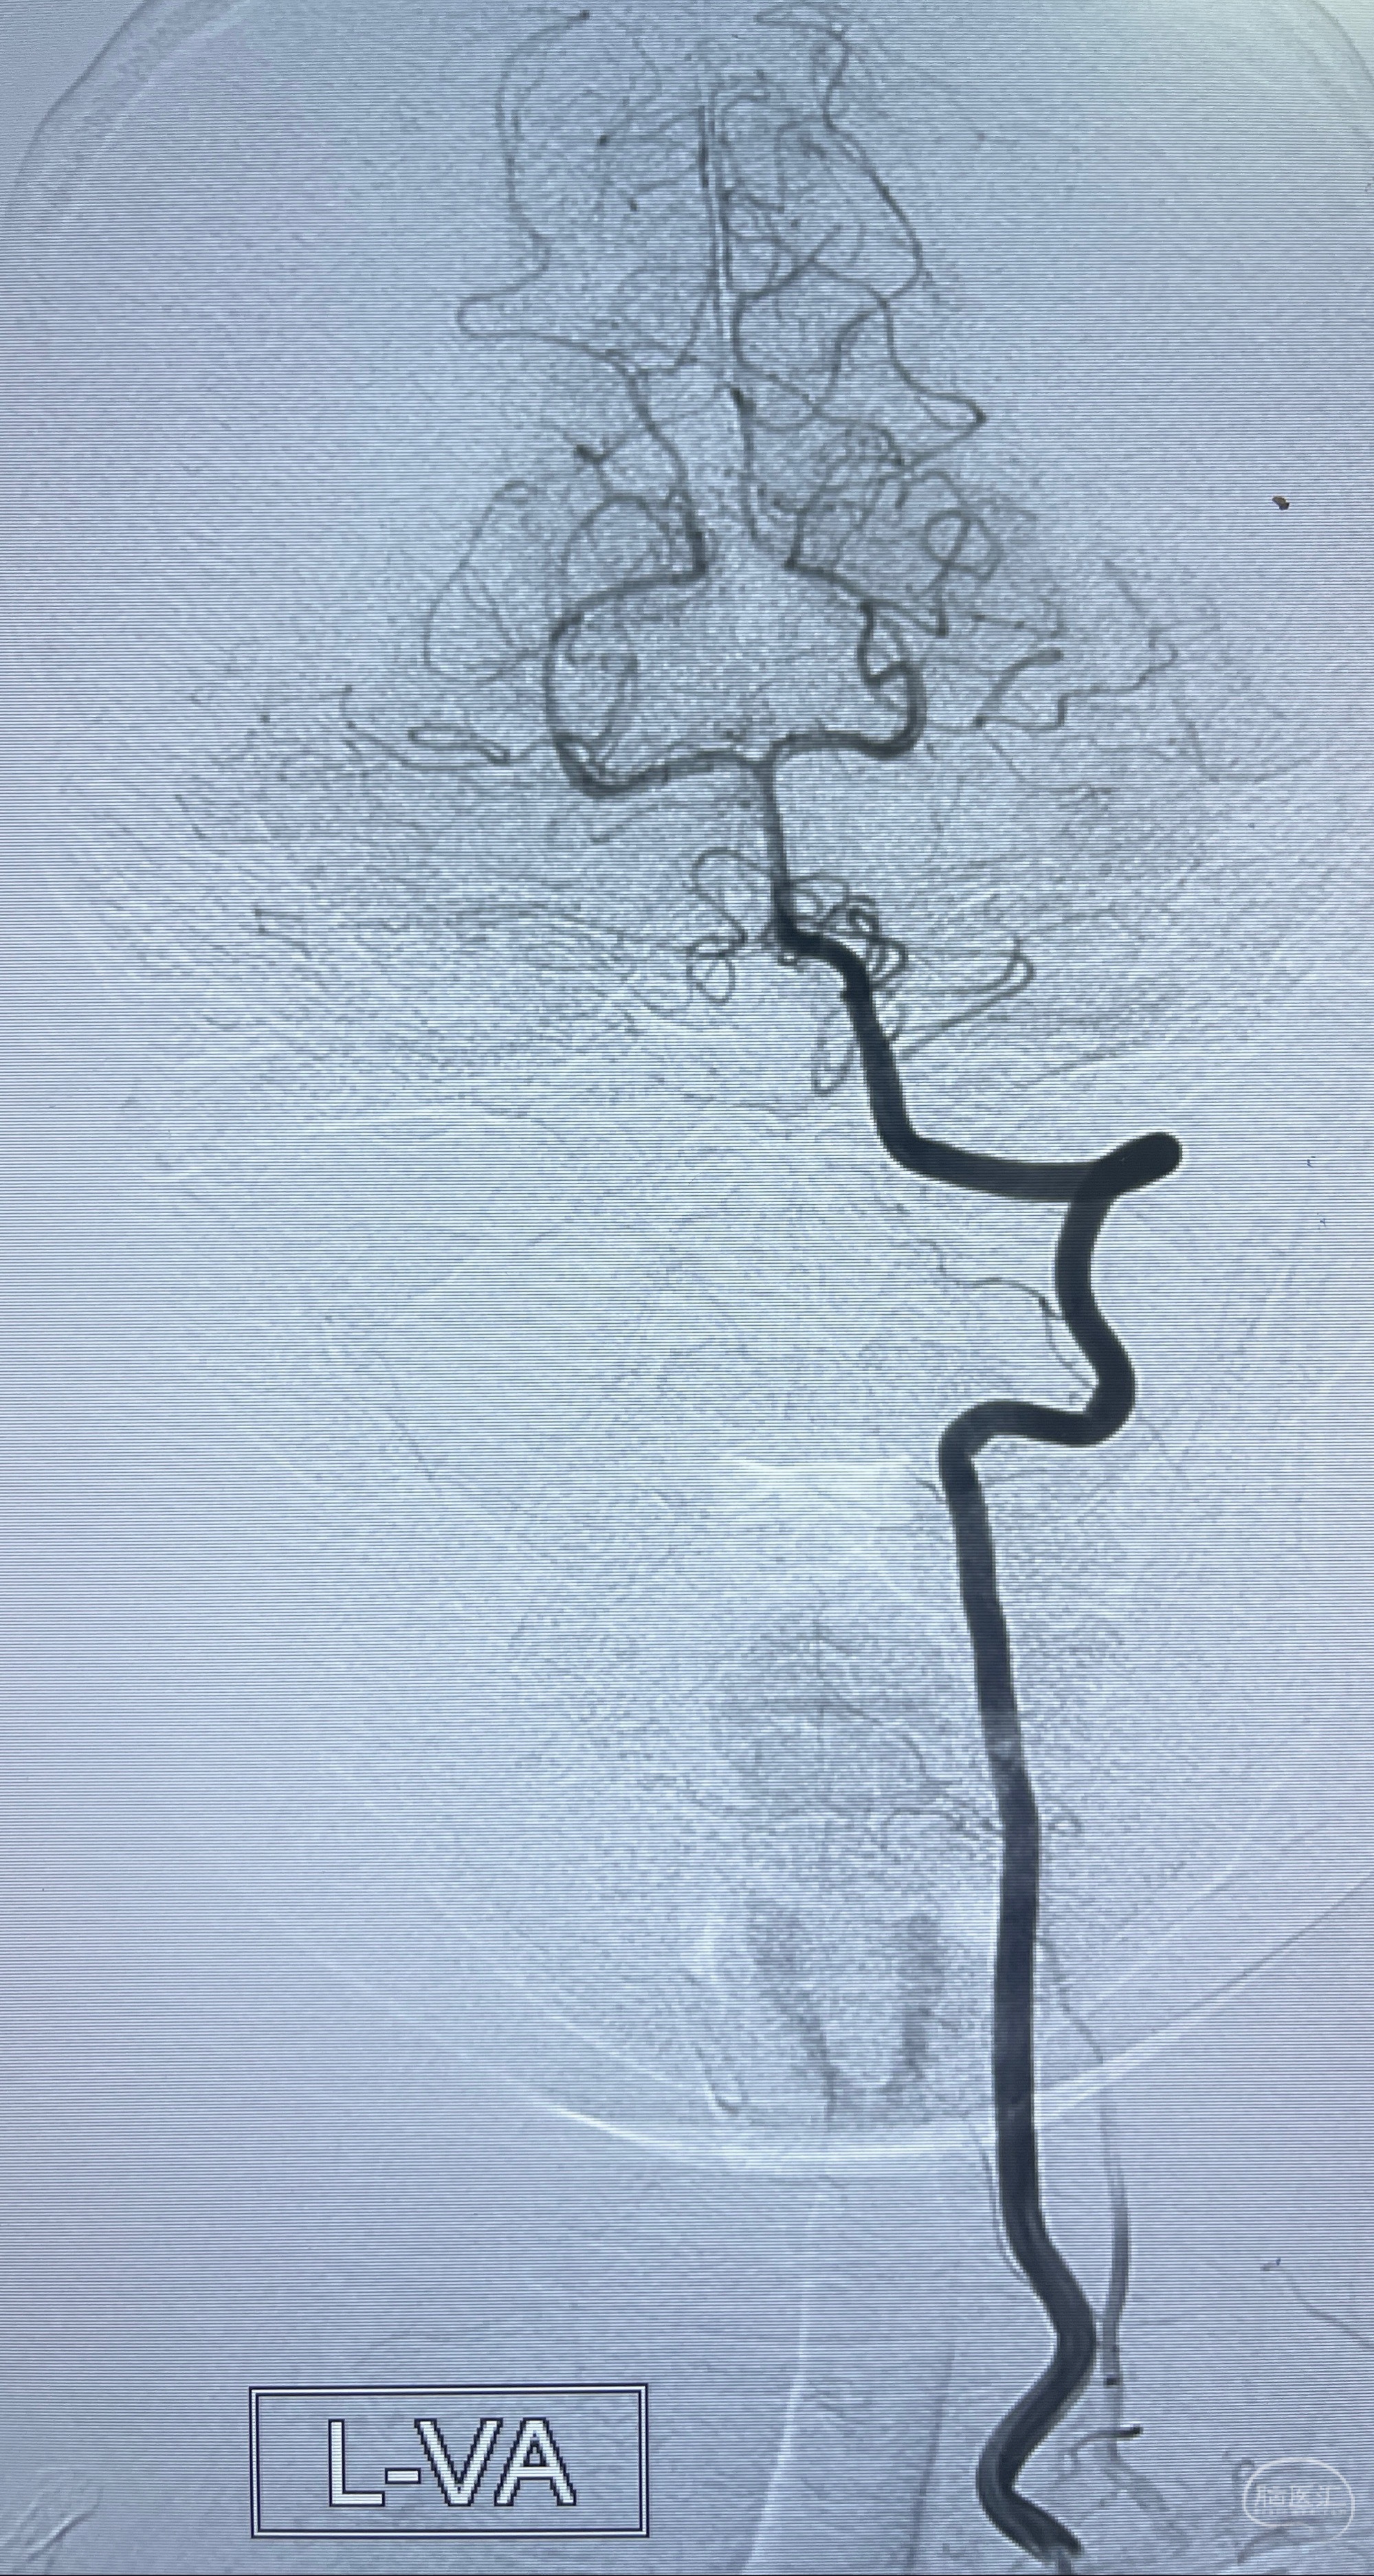

2023-07-27全脑血管造影:双侧颈内动脉眼动脉段动脉瘤,右侧较大

2023-08-01全麻下行双侧颈眼动脉瘤支架辅助栓塞